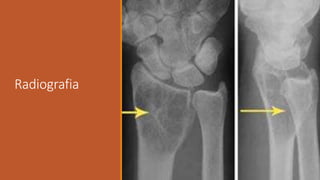

Avaliação de Radiografias do

Sistema Musculoesquelético

1- Identificar os aspectos técnicos da radiografia:

Posicionamento no negatoscópio: A radiografia é colocada

com a etiqueta à esquerda do observador.

Eventualmente o técnico em radiologia pode acrescentar o

sinal “D” ou “R” para facilitar a identificação do lado direito e

“E” ou “L” para o esquerdo.

Avaliação de Radiografias do Sistema

Musculoesquelético

Região examinada: Geralmente descrevemos o osso

(fêmur, tíbia, radio...), a articulação (quadril, joelho,

cotovelo...) ou a região (bacia, coluna cervical...).

- Incidência: o exame de cada região deve ser realizada em

pelo menos duas incidências, preferencialmente

anteroposterior e perfil (AP + P). Outras: oblíquas e axiais.

2- Identificar os aspectos gerais do exame:

Identificar o que mais chama atenção na radiografia.

Em sequência observamos os seguintes parâmetros:

a) Contorno ósseo,

b) Formato do osso,

c) Textura do osso

d) Partes moles.

3-Identificar as particularidades das alterações encontradas:

Aspectos específicos

Alteração ou lesão significativa: caracterizar as

particularidades desta lesão e definir o diagnóstico.

Onde está a lesão?

Qual o tamanho da lesão?

O que a lesão está produzindo no osso?

Qual a resposta do osso?

Há lesão do córtex?

Quais as características da matriz da lesão?

Há massa de partes moles?